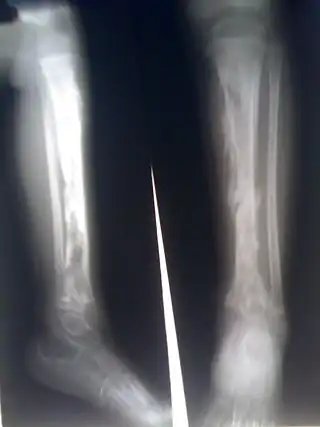

![]() Osteomielitis en la tibia de un escolar, apreciándose numerosos abscesos que aparecen como luminosidad en la radiografía. | ||